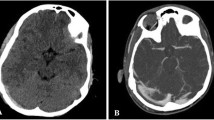

9 Pathophysiology of Neurogenic Pulmonary Edema

Neurogenic pulmonary edema (NPE) is a dreadful complication that occurs following various intracranial injuries such as intracranial and subarachnoid hemorrhage, traumatic brain injury, spinal cord injury, and refractory status epilepticus [25,26,27,28,29,30]. This clinical condition usually presents with tachypnea, tachycardia, hypertension, and bilateral basal pulmonary crepitation and even hemoptysis [29, 31]. It is often called as “death rattle” [31] due to its presentation of severe respiratory distress, pulmonary edema with normal jugular venous pressure, and severe hypoxemia [29]. The appearance of bilateral diffuse infiltrates on the chest X-ray within minutes to hours after the CNS injury is the most pathognomonic finding for the diagnosis [29]. The precise mechanism underlying this condition is incompletely understood; however, dissociation of the pulmonary autonomic system from the central vasomotor center and overstimulation of the CNS trigger zone that has been associated with excessive sympathetic discharge are the two commonly proposed mechanisms [32]. Studies have shown that the NPE does not initiate any systemic inflammatory response, as demonstrated by the lack of damage to organs other than lungs, and it is treated with adequate positive end expiratory pressure [32]. The pathophysiology of development of NPE is explained in Fig. 17.2.